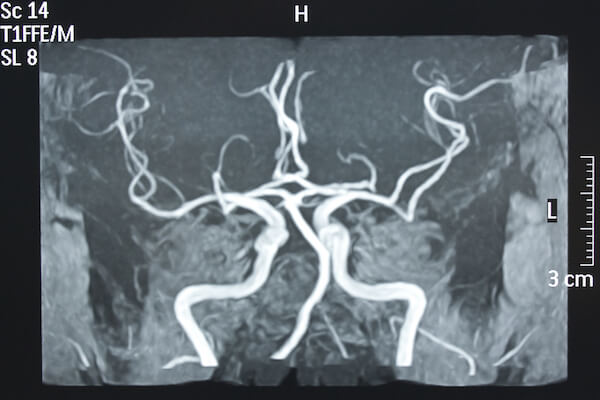

The femoral artery is accessed through catheters that have the task of engaging the aortic arch and subsequently the epiaortic vessels, until they reach the site to be treated.

Once the target is reached, other devices such as microcoils, stents or embolizing agents are inserted, depending on the pathology.